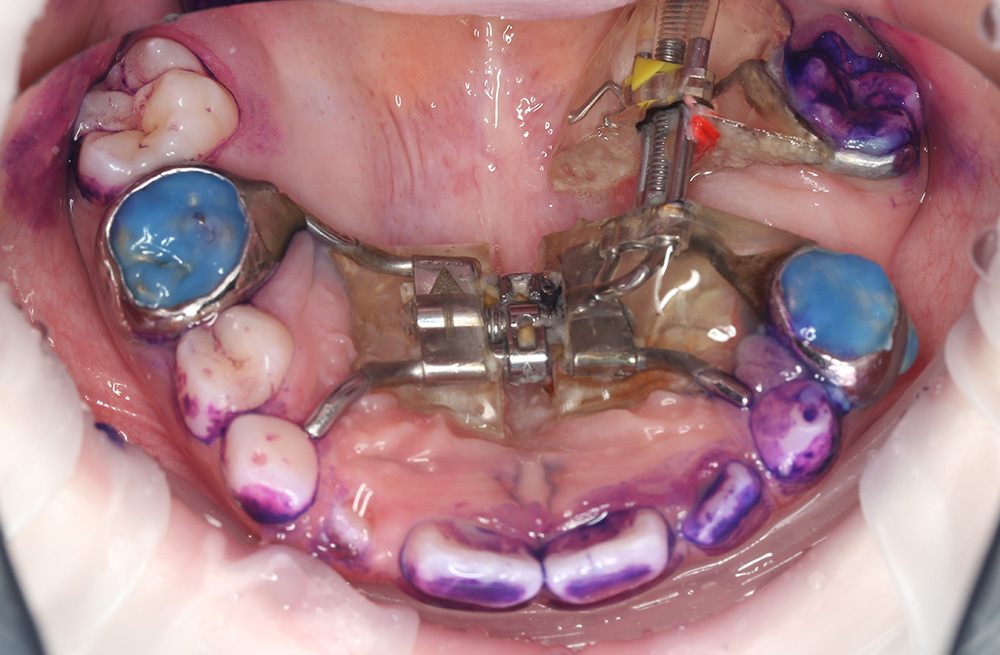

Лечение и восстановление зубов во сне за один визит ребенку 6 лет